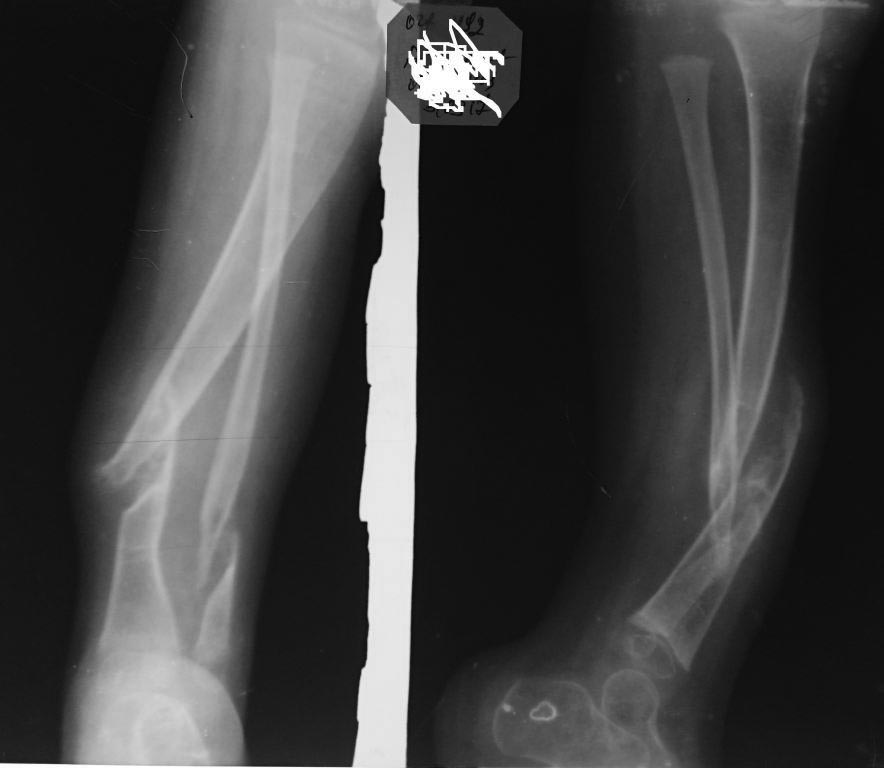

Спасибо за информацию уважаемый Никита. Очень многое прояснилось. Но у меня ощущение что мы говорим о разных псевдоартрозах. Я имею ввиду истинный атрофичный псевдоартроз на почве нейфиброматоза, а не на почве фиброзной дисплазии или миелодиспластического характера. Про посттравматический или патологический на фоне несовешенного остеогенеза тоже не имею виду.

У вас как то все просто))))) и слава богу но вот по данным Grill et al при применении метода Илизарова сращение было у 75% детей при этом не сказано в статье про процент от вида ложного сустава. То есть получается у каждого 4 ребенка. В приложении фото последнего ребенка кого хочу прооперировать но пока дал отбой.

Пример будущего пациента